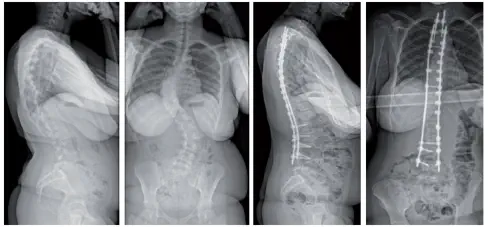

14 Jahre, adoleszente idiopathische Skoliose mit doppelter starker Krümmung, T2/L4 Arthrodese mit Jazz Frame-Fixation.